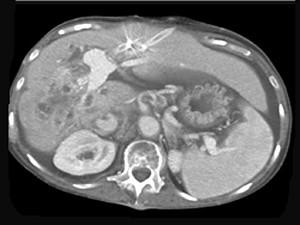

问题 男,50岁,右上腹痛,进行性黄疸,无腹部包块,AFP阴性,影像检查如图,最可能的诊断是 ( )

选项 A、肝腺瘤 B、肝转移瘤 C、胆管癌 D、肝血管瘤 E、肝细胞肝癌

答案 C